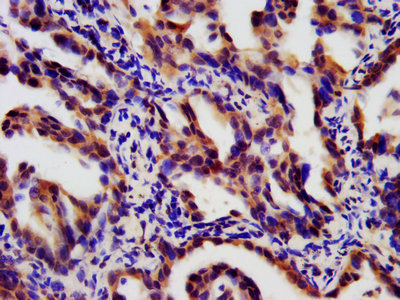

LTBR 屬于Ⅰ型單跨膜蛋白 [1],是腫瘤壞死因子受體(TNFR)家族的成員 [2]。完全糖基化的LTBR分子量為61kDa,去除糖基化修飾后,理論分子量降至47kDa [3]。其胞質(zhì)結(jié)構(gòu)域由 175 個氨基酸組成,靠近細胞膜區(qū)域富含脯氨酸殘基,這一結(jié)構(gòu)特點使其能像其他TNFR家族蛋白一樣,直接與腫瘤壞死因子受體相關(guān)因子(TRAF)蛋白相互作用,在細胞信號傳導(dǎo)中發(fā)揮關(guān)鍵作用 [4]。LTBR蛋白結(jié)構(gòu)包括胞外區(qū)、跨膜區(qū)和胞內(nèi)區(qū)(圖 1)。胞外區(qū)負責與配體結(jié)合,識別特定信號分子;胞內(nèi)區(qū)則通過與TRAF蛋白相互作用,啟動細胞內(nèi)信號傳導(dǎo)通路,進而調(diào)控細胞的生物學行為 [5]。

圖1:LTBR蛋白的結(jié)構(gòu)組成

圖源:https://www.uniprot.org/uniprotkb/P36941/entry